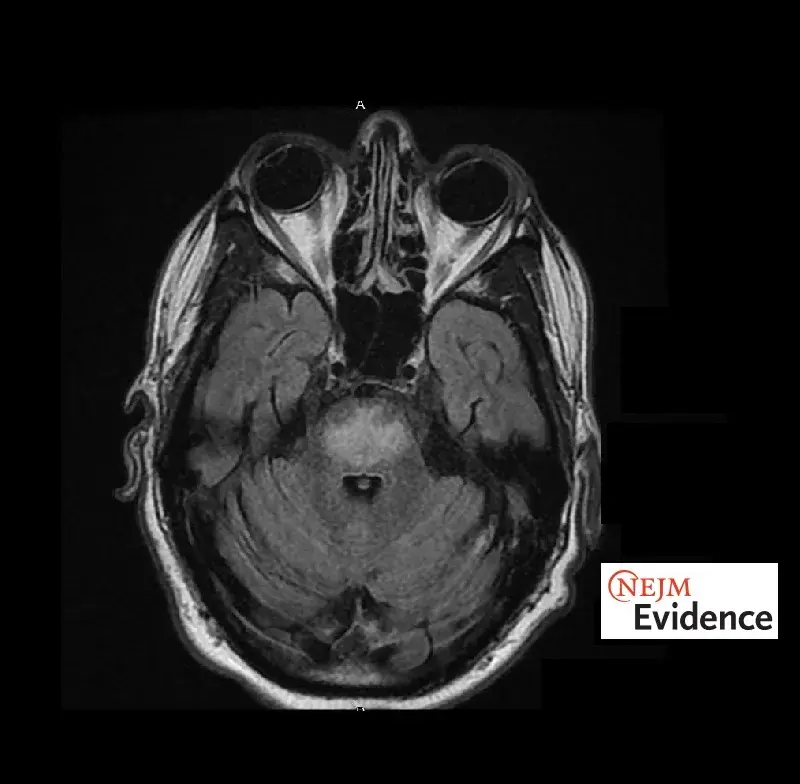

glomerulopatias

nefrite lupica